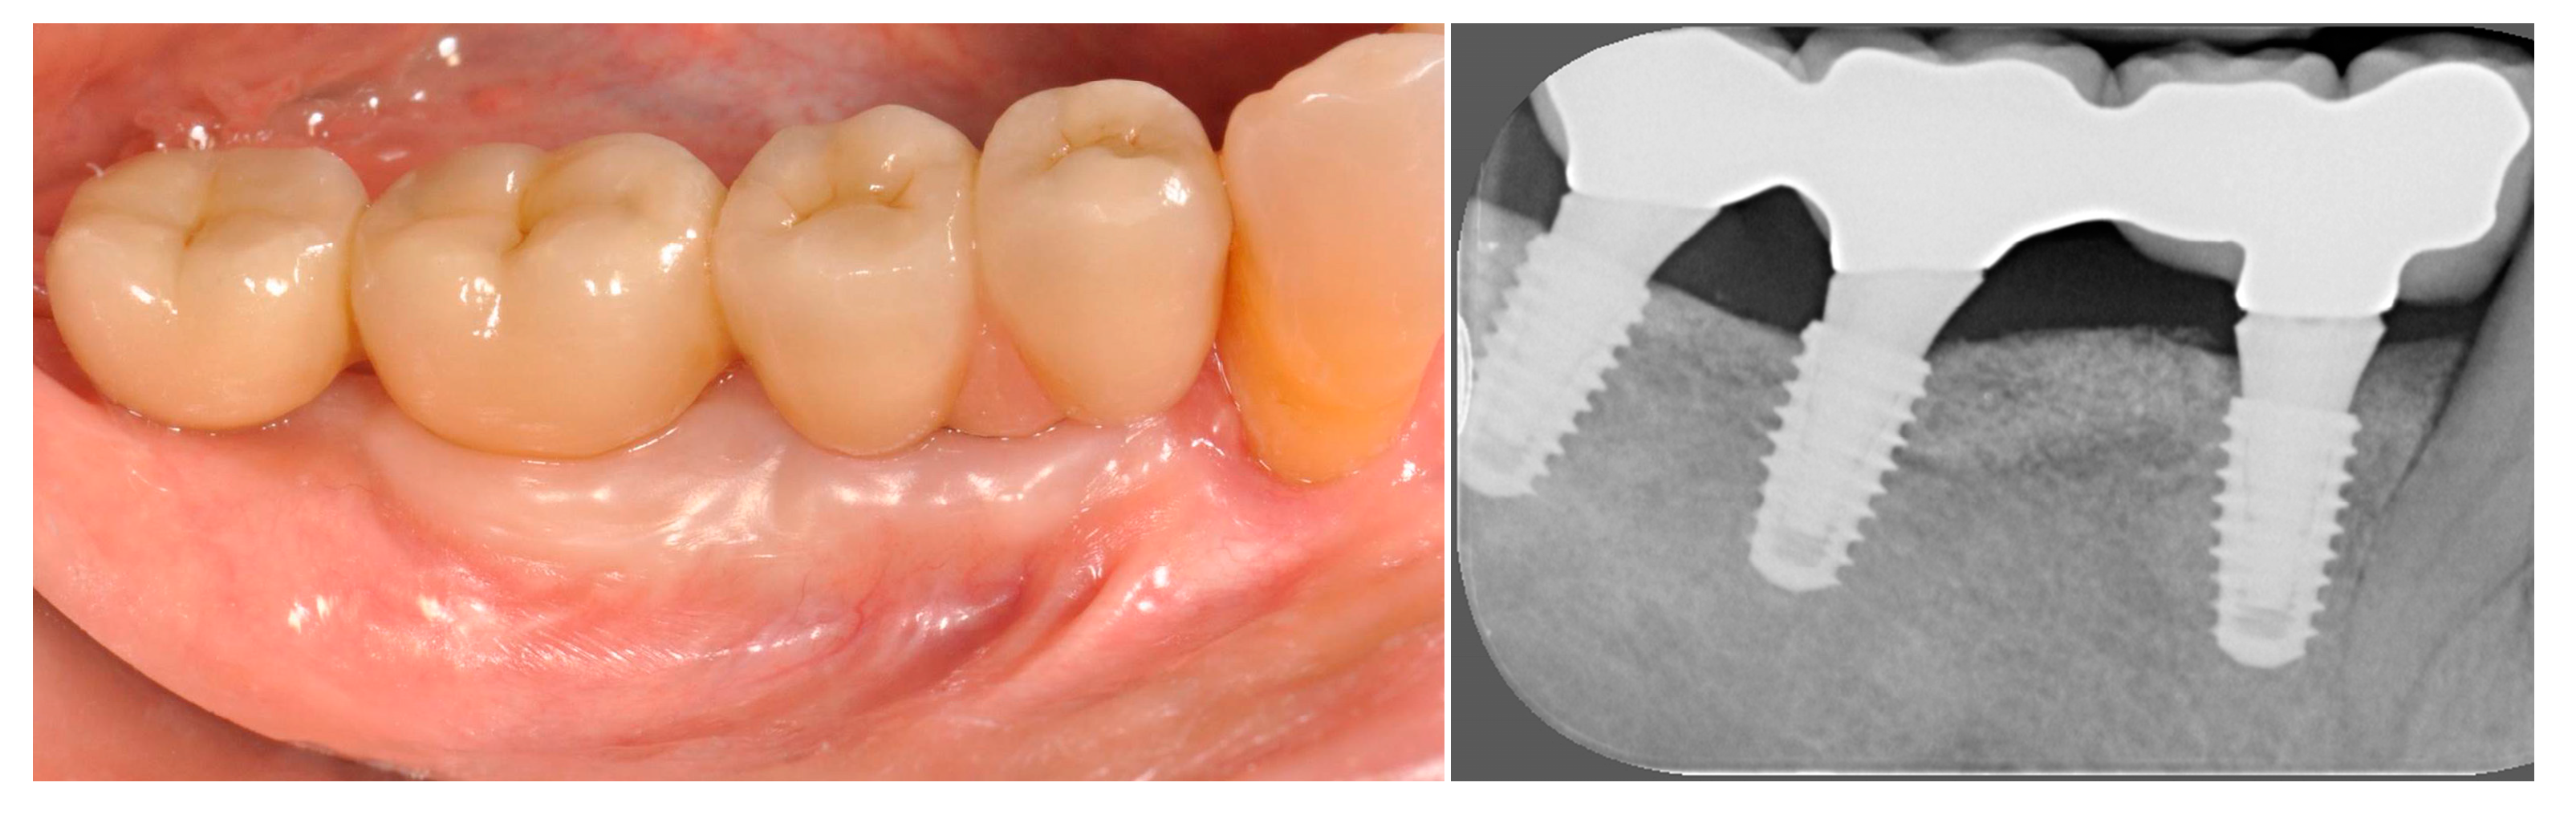

3.2. Fixed Partial Prostheses